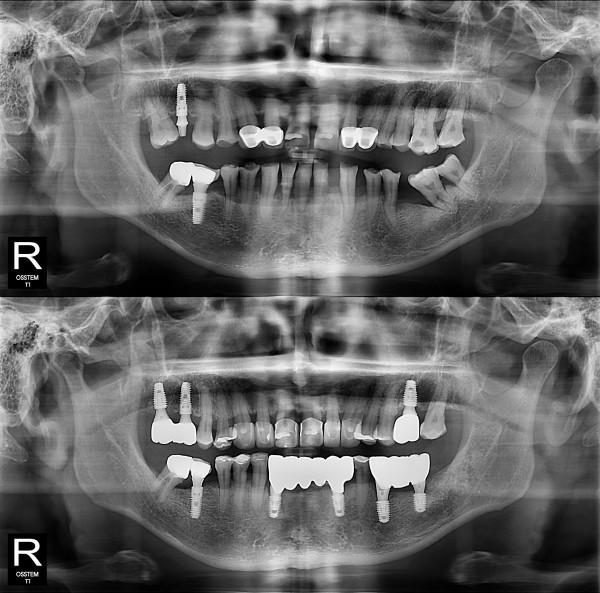

임플란트

부분 임플란트